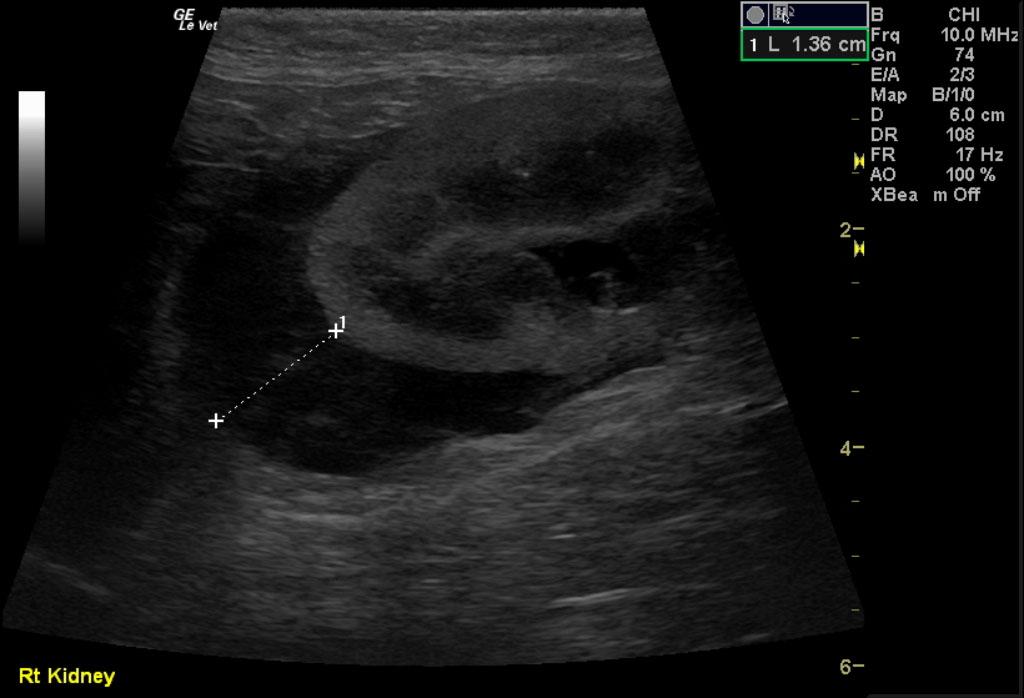

Image 1 & Video 1: The liver was moderately enlarged, rounded in shape having mildly hypoechoic echogenicity with multifocal hypoechoic and cystic nodules throughout. The gallbladder was normal in size, shape, and clean. Images 2-4 & Video 2-4: The left and right kidneys were severely enlarged with mild hydronephrosis in the right kidney. Both kidneys had hyperechoic cortices with large hypoechoic caps surrounding and invading the renal cortices (left kidney cap-7.4 mm in thickness, right kidney cap-13.6 mm in thickness). Image 5 & Video 5: Stomach: mucosal layer is mild/moderately thickened with overall wall thickness measuring 3.8 mm. Images 6: Intestine: there is focal mucosal layer thickening measuring up to 5.1 mm while the rest of the intestinal loops are of normal thickness. Video 6: Colon: the colonic wall appeared thickened at the ileocecolcolic junction. Image 7: Lymph Nodes: Multiple mesenteric lymph nodes were severely enlarged throughout the abdomen. The epigastric LN enlargement is shown in this image in the near field.